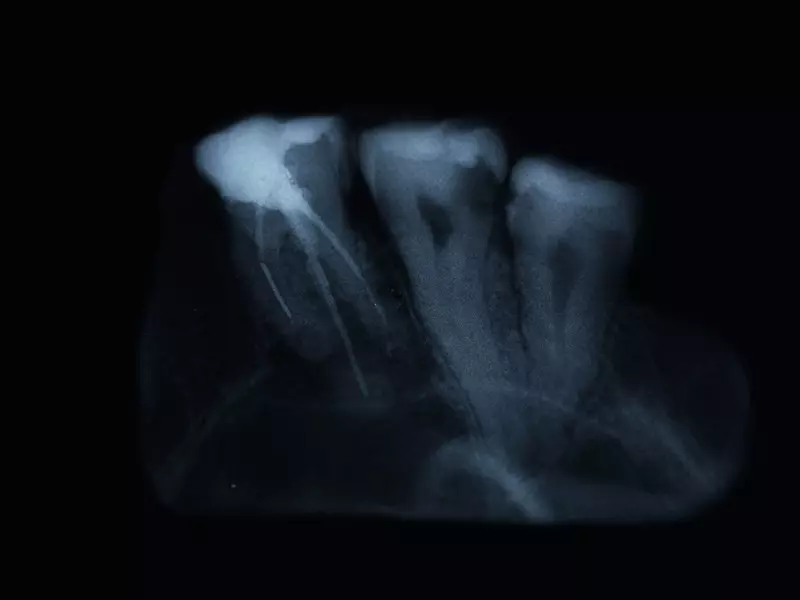

Diagnostyka

Według Paradowskiej-Stolarz i wsp. diagnostyka zęba zatrzymanego powinna obejmować zarówno badanie kliniczne (brak wyrżnięcia się zęba w odpowiednim dla niego czasie), jak i badanie radiologiczne. Autorzy podkreślają, że badaniem przesiewowym w tym przypadku jest zdjęcie pantomograficzne, jednak do pełnej diagnostyki niezbędne jest wykonanie tomografii komputerowej. Dopiero taka projekcja dostarcza pełnej informacji dotyczącej usytuowania zęba zatrzymanego oraz umożliwia zobrazowanie sąsiadujących z nim struktur, a także umożliwia zaplanowanie zabiegu chirurgicznego.